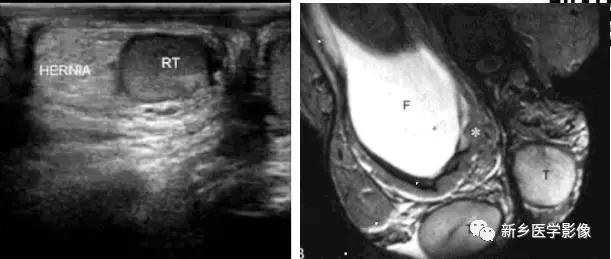

(十六)腹股沟斜疝

临床表现:临床症状可因疝囊大小或有无并发症而异。基本症状是腹股沟区出现一可复性肿块,开始肿块较小,仅在患者站立、劳动、行走、跑步、剧咳或婴儿啼哭时出现,平卧或用手压时肿块可自行回纳。一般无特殊不适,仅偶尔伴局部胀痛和牵涉痛。随着疾病的发展,肿块可逐渐增大,自腹股沟下降至阴囊内或大阴唇,行走不便和影响劳动。肿块呈带蒂柄的梨形,上端狭小,下端宽大。

(十二)先天异常隐睾症

单侧或双侧阴囊内未探及*丸睾**回声。于腹股沟或腹膜后探及一低回声、卵圆形团块,边界清楚。位于腹股沟内者可移动。有的隐睾周围可见少量鞘膜积液。当合并炎症或扭转时,*丸睾**增大,回声不均,有明显触痛,常伴鞘膜积液。恶变时,*丸睾**增大,近圆形,实质回声强弱不均,有的可见低回声团块。CDFI:急性炎症可见血供增多,而扭转则无血流信号。恶变的*丸睾**血供丰富。小于2cm的单纯隐睾,一般不易探及血流信号。